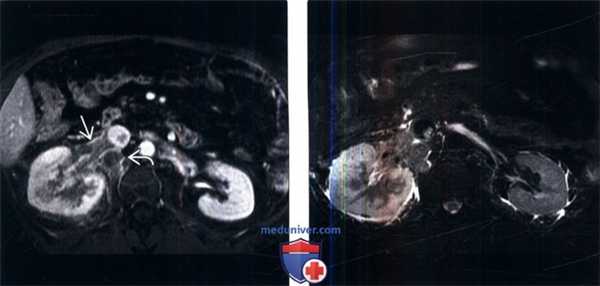

(Слева) МРТ, постконтрастное Т1-ВИ, аксиальная проекция: у мужчины 59 лет, в анамнезе у которого имеется образование правой почки, выявлен обширный тромбоз правой почечной вены с продолжением в НПВ и поясничную ветвь. Обратите внимание на увеличение правой почки и отсроченную нефрограмму вследствие венозного тромбоза.

(Справа) МРТ, Т2-ВИ, аксиальная проекция: у этого же пациента выявлен измененный Т2-сигнал от правой почки вследствие венозного тромбоза и перегрузки. При патоморфологическом исследовании был подтвержден светлоклеточный ПКР.